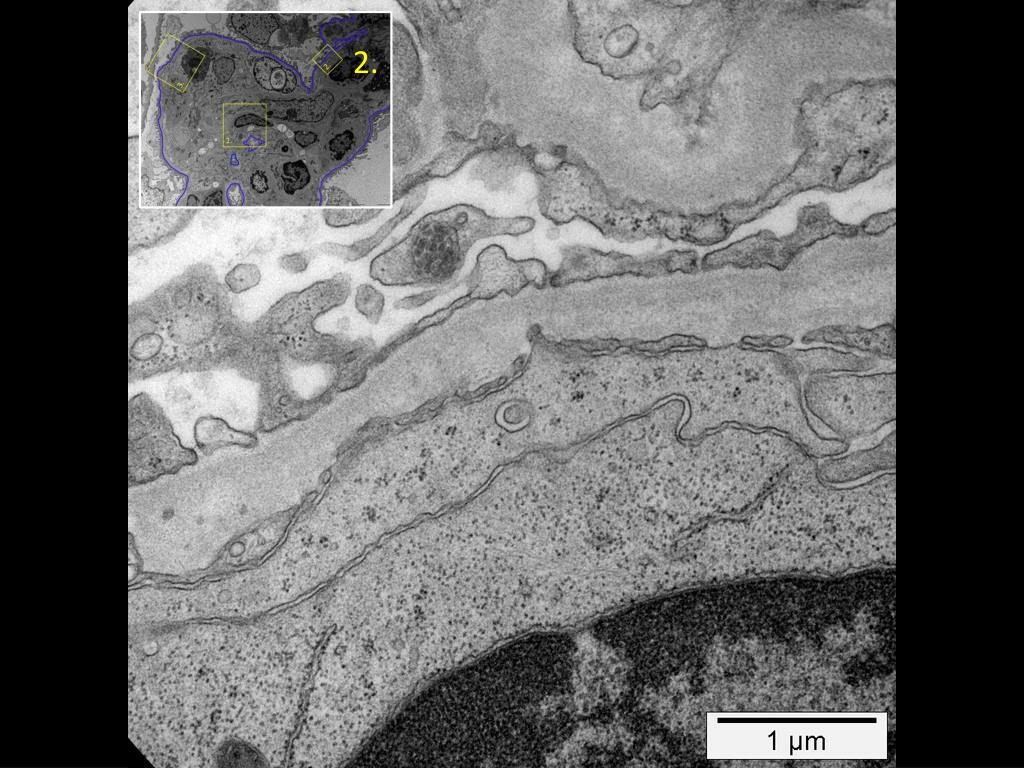

7. 2. 1. 3.

8. 1.

9. 2.

10. 3.